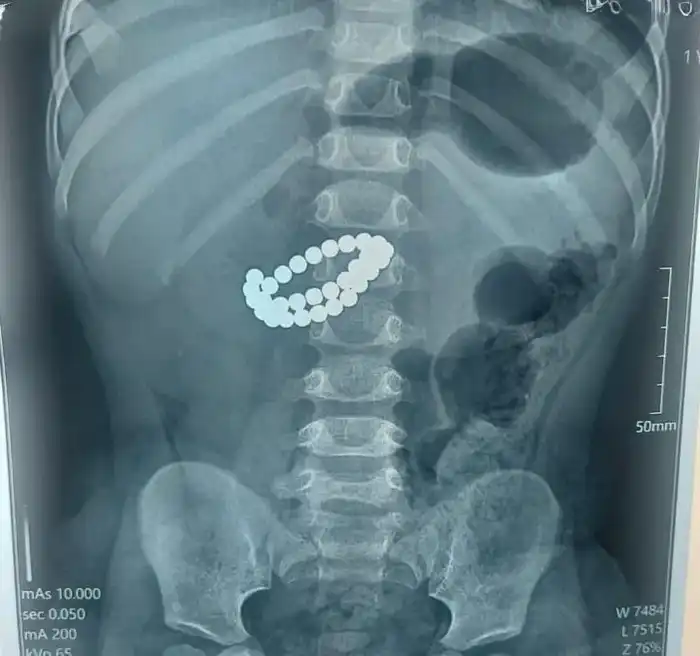

В Алматы медицинские работники провели экстренную операцию для спасения малыша, который проглотил 31 магнит. Информация об этом поступила из управления общественного здравоохранения города, где сообщили, что ребенок в возрасте 1 года 9 месяцев был доставлен в крайне тяжелом состоянии.

После тщательного обследования врачи выявили наличие 31 магнита в кишечнике, множественные перфорации тонкой кишки и диффузный каловый перитонит. Для спасения жизни ребенка было решено провести срочное хирургическое вмешательство, в ходе которого хирурги выполнили срединную лапаротомию и провели ревизию органов брюшной полости.

Хирург Аскар Ризванов, работающий в Центре детской неотложной медицинской помощи Алматы, подчеркнул, что магниты, попадая в организм, начинают притягиваться друг к другу. Это создает опасные условия: стенки кишки зажимаются между магнитами, что может привести к нарушению кровообращения и некрозу тканей, в результате чего формируются отверстия и развивается перитонит.